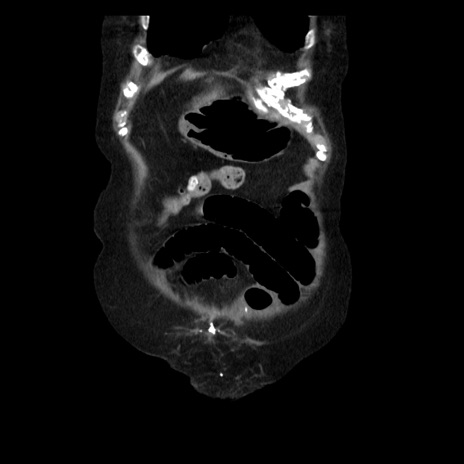

症例14(冠状断像)

【症例】 90歳代女性

【主訴】 腹痛・嘔吐

【現病歴】今朝から左側腹部痛を認めた。 経過観察していたが、嘔吐を認めたため来院。

【既往歴】 子宮癌術後

【身体所見】 意識清明、BP 127/54mmHg、P 98bpm Sp02 95%(RA)、BT 35.8°C、腹部平坦・軟腸ぜん動音聴取良好、右下腹部圧痛(+) 反跳痛なし

【データ】WBC 9800、CRP 0.46